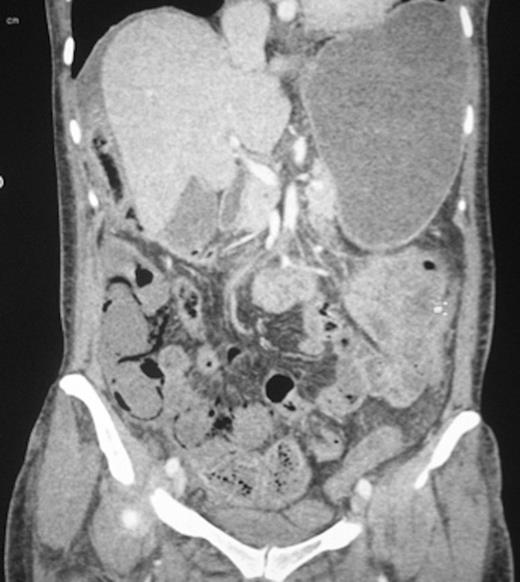

The patient subsequently underwent computed tomography (figure 2).